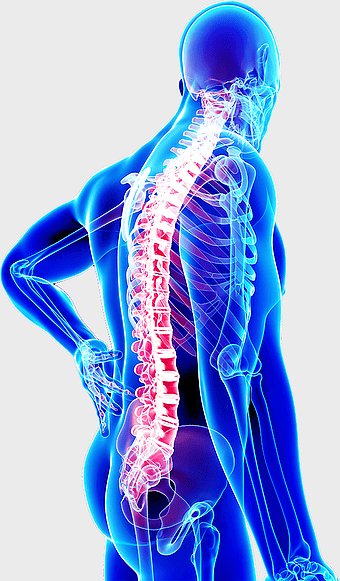

Human skeleton, rib cage anatomy, upper limb bones, joints in human body, skeletal structure analysis, vertebral column details, anatomical illustration study -

spine skeleton illustration, orthopedic surgery, musculoskeletal disorder, human body anatomy, skeletal health, medical imaging, spine health analysis -